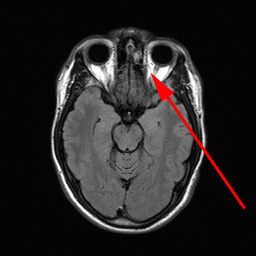

Øjne, normal, MR

Horisontalt snit fra en MR-scanning på højde med øjnene

Ovenfor ses en MR optagelse i form af et tværsnit gennem hovedet på højde med øjnene. Den røde pil peger på synsnerven i den ene side.